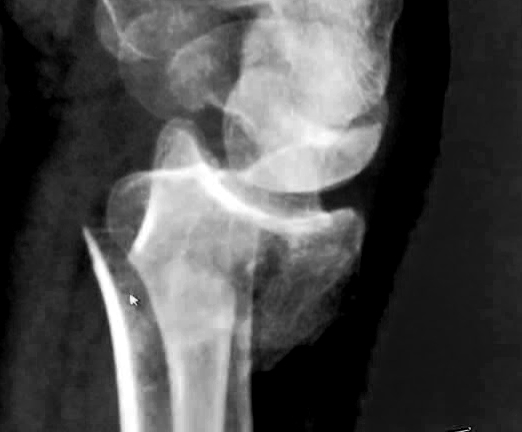

Having traversed the country from Lands End to John O'Groats, the continent from Calais to Marseilles, peddaled a few thousand miles across Canada, sprinted around the London 100 mile olympic circuit and mastered various mountain trails, Simon conspired to fall of his bike at the bottom of East Hill and broke his wrist. Fortunately his left wrist. Come in St Peter's. It's only 15 minutes away.

Returning to Gatwick we were due to be collected by Simon, whose wrist by then allowed him to drive even if he was still nervous on his bike. He rang to say where he was waiting, I answered the phone and told Pat who turned as I told her he was waiting. Unfortunately we were on the travellator and very near the end of travel. It stopped before we did. Pat - facing the wrong way - fell: I hurdled her and landed right on her specs. Wire frames are not built to withstand hurdlers. But much worse was that Pat was hurt and in pain. We stopped at Simon's house and from there to St Peter's Hospital, returning home hours later with diagnosis and plaster.